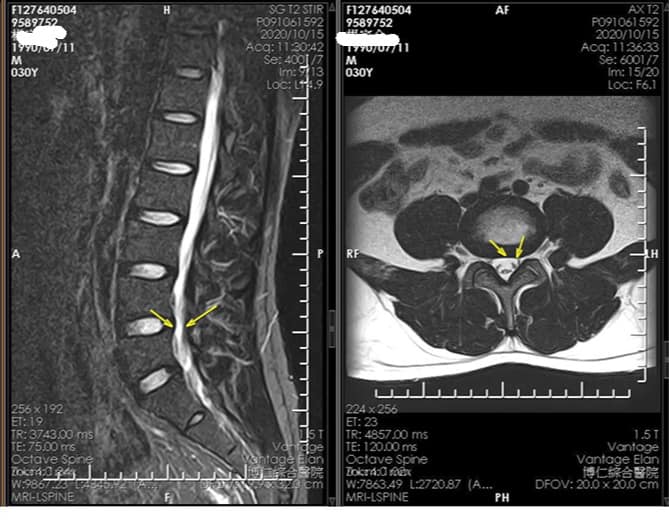

Cervical Spine Treatment Cases 腰椎治療案例 #腰椎手術失敗綜合症候群 #術後沒保養還是又繼續椎間盤突出 #感謝台北梁小姐熱情見證 ... 2021.03.02 #超感動醫案感謝中壢姚阿姨見證 #原本已經坐輪椅的人生看到一絲希望 #脊刻救援牛轉乾... 2021.02.22 #感謝新北中和區陳大哥熱情見證 #從北到南看過眾多中西醫民俗療法 #腰痛到連躺跟坐都... 2021.02.17 #感謝桃園龜山蘆先生熱情見證 #腰椎跟屁股痠痛超過十二年 #腰椎纖維環裂隙導致神經根... 2021.02.16 #騎馬摔傷腰椎醫案 #感謝內湖陳先生熱情見證 #椎間盤突出合併輕微椎間孔狹窄 #重新騎... 2021.02.03 #巨大椎間盤突出醫案 #脊椎整合中醫微創逆轉勝 #感謝三峽林先生熱情見證 #為何突出的... 2021.01.29 #腰椎粉碎性骨折手術後調養醫案 #坐輪椅的人生終於看到希望 #脊椎手術失敗症候群 #Fai... 2021.01.26 #感謝台中市大肚區患者熱情見證 #第二次治療腰痛好超多 #腰酸痛時間快一年了 #親筆寫... 2020.12.05 #腰椎嚴重滑脫醫案 #原本左腳麻痛無法久站超過十分鐘 #脊椎整合中醫微創療法逆轉勝 #... 2020.12.02 #感謝林口楊先生熱情見證 #椎間盤整和中西醫微創療法逆轉勝 #曾經大痛到無法走路嚴重... 2020.11.25 #今天來聊巨大骨刺為何可以吸收回去! #椎間盤突出需要多久才能吸收呢? #馬尾神經症候... 2020.11.10 #腰椎滑脫一定要開刀嗎? #骨科認為開刀置放骨釘穩定錐體 #如果患者可以藉由增強肌... 2020.11.04 #六年的長期腰酸痛醫案 #原來是椎管狹窄合併輕微突出 #每年冬天準時發作苦不堪言 #感... 2020.10.31 #椎管狹窄案例 #感謝新莊陳大哥熱情見證 #腰酸痛數年原來是椎管狹窄 #來診前已經痛到... 2020.10.28 #知名四代魚丸店掌門人熱情見證 #腰椎中醫微創逆轉勝 #椎間盤突出醫案 #感謝新北... 2020.10.23 ← 上一頁 8 9 10 11 12 下一頁 →